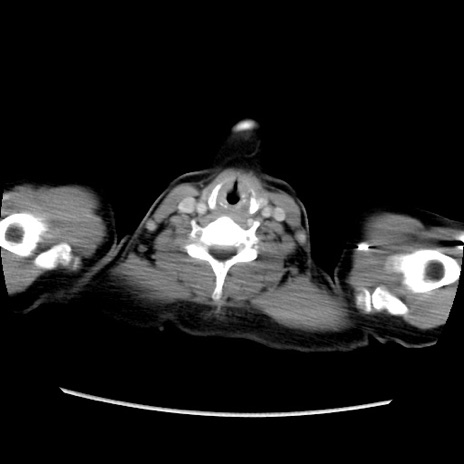

症例39(横断像)

【症例】40歳代女性

【主訴】上下腹部痛

【現病歴】2日目から下腹部痛あり。夜間は痛みで眠れなかった。昨日より上腹部痛と下痢が出現。臥位で痛みは軽快したため、休んでいた。本日になって臥位でも立位でも痛みが強くなってきたため救急要請。

【既往歴】子宮内膜症

【身体所見】部:平坦・軟、左上下腹部に圧痛あり、反跳痛あり。

【データ】WBC 21800、CRP 26.78